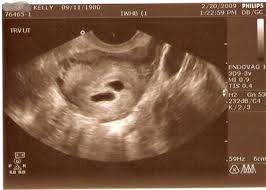

Can a blighted ovum cause an early miscarriage? Nov 10, 2020 · how long can you carry a blighted ovum? Many women need support and time to grieve. It's also called anembryonic pregnancy or empty sac. What to do with a blighted ovum pregnancy? The placenta and sac still give off pregnancy hormones. Dec 13, 2017 · the sonogram will show the placenta and empty embryonic sac. While you can technically get pregnant again as soon as your periods return, we recommend that you wait for about three months to fully heal after a miscarriage.

Dec 13, 2017 · the sonogram will show the placenta and empty embryonic sac. While a blighted ovum leads to loss of pregnancy, most women tend to have healthy pregnancies and babies subsequently. What are the treatment options? Nov 10, 2020 · how long can you carry a blighted ovum? While you can technically get pregnant again as soon as your periods return, we recommend that you wait for about three months to fully heal after a miscarriage. A miscarriage is when a pregnancy ends on its own within the first 20 weeks. How long can a blighted ovum pregnancy last? These cause a pregnancy test to show positive, and can give you symptoms of pregnancy. You have a placenta and a gestational sac, but the embryo doesn't grow. Your body understands the pregnancy is not developing properly and starts to shed blood and tissue from the uterus. It's also called anembryonic pregnancy or empty sac. Blighted ovum is a type of early pregnancy loss. Experiencing a miscarriage for any reason is painful.